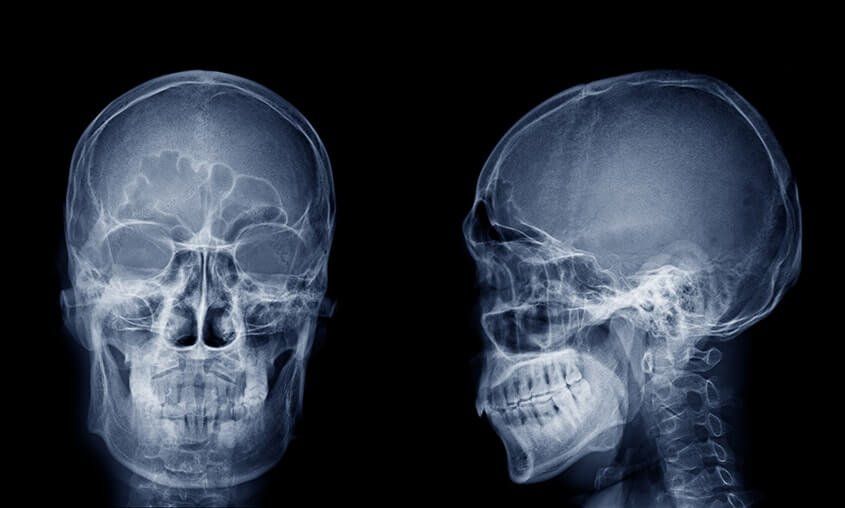

From www.istockphoto.com

Film Xray Skull Radiograph Show Adenoid Hypertrophy Enlarged Adenoid In Sleep Apnea X Ray Symptoms are insidious and diagnosis is usually delayed. Obstructive sleep apnea (osa) is characterized by. Upper airway imaging is currently not part of the routine diagnostic evaluation for obstructive sleep. sleep apnea, obstructive / diagnostic imaging. this guideline establishes clinical practice recommendations for the diagnosis of obstructive sleep apnea (osa) in adults and is intended for use in.. Sleep Apnea X Ray.

From www.researchgate.net

Cephalometric planes (oropharynx and laryngopharynx) for sleep apnea Sleep Apnea X Ray Symptoms are insidious and diagnosis is usually delayed. Obstructive sleep apnea (osa) is characterized by. obstructive sleep apnoea (osa) is characterised by recurrent upper airway collapse during sleep resulting in chronic and repetitive hypoxia, hypercapnia, subsequent arousal and fragmented sleep. sleep apnea, obstructive / diagnostic imaging. the diagnosis of osa is confirmed by polysomnography. this guideline. Sleep Apnea X Ray.